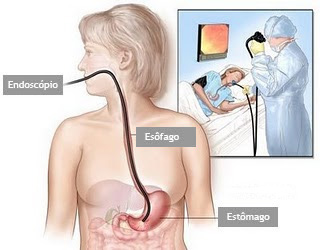

É um exame indicado para avaliação diagnóstica e tratamento das doenças da parte superior do tubo digestivo, incluindo o esôfago, o estômago e a porção inicial do duodeno.

Realizado introduzindo-se pela boca um aparelho flexível com iluminação central que permite a visualização de todo o trajeto examinado.

O exame é realizado com anestesia tópica (um spray de anestésico na garganta) e com sedação, utilizando medicação administrada por uma veia para permitir que você relaxe e adormeça.

É um exame indicado para avaliação diagnóstica e tratamento das doenças da parte superior do tubo digestivo, incluindo o esôfago, o estômago e a porção inicial do duodeno.

Realizado introduzindo-se pela boca um aparelho flexível com iluminação central que permite a visualização de todo o trajeto examinado.

O exame é realizado com anestesia tópica (um spray de anestésico na garganta) e com sedação, utilizando medicação administrada por uma veia para permitir que você relaxe e adormeça.